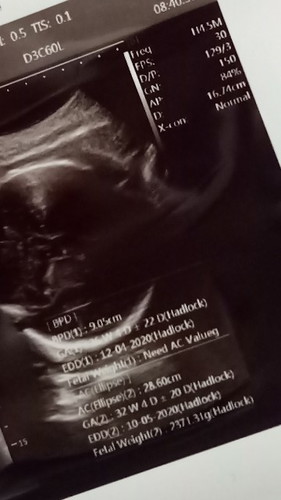

HPL hasil USG

Bunda, yang di baca HPL dari USG yg mana ya...?? Tolong bun, kasih tau maaf gx mudeng.. Hehe Kira kira baiknya cuti tgl brpa ya bun, kerjanya jauh dri rmah suami kayak males nganterin..

Bunda pernah usg ga wktu TM1 ?? Klo pernah, ikutin hpl usg wktu TM 1 aja